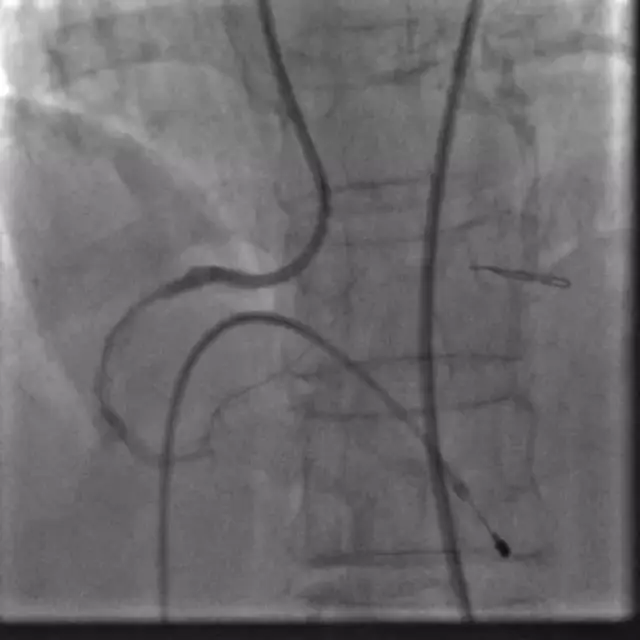

冠脉内支架脱载的处理及预防策略_南方医科大

699x402 - 824KB - BMP

例」PCI术后血压降至61\/34 mmHg,真相是啥?